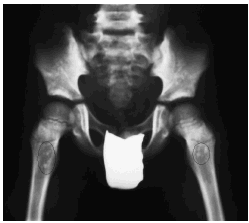

En una radiografía simple de caderas y miembros superiores se encontraron lesiones escleróticas de osteopoiquilosis en muñecas y pelvis (fig. 3). En el estudio radiológico efectuado a los padres y hermanos del paciente se hallaron lesiones óseas escleróticas en la madre, en las manos (fig. 4) y miembros inferiores.

Fig. 3.--Lesiones de osteopoiquilosis en las caderas del paciente.